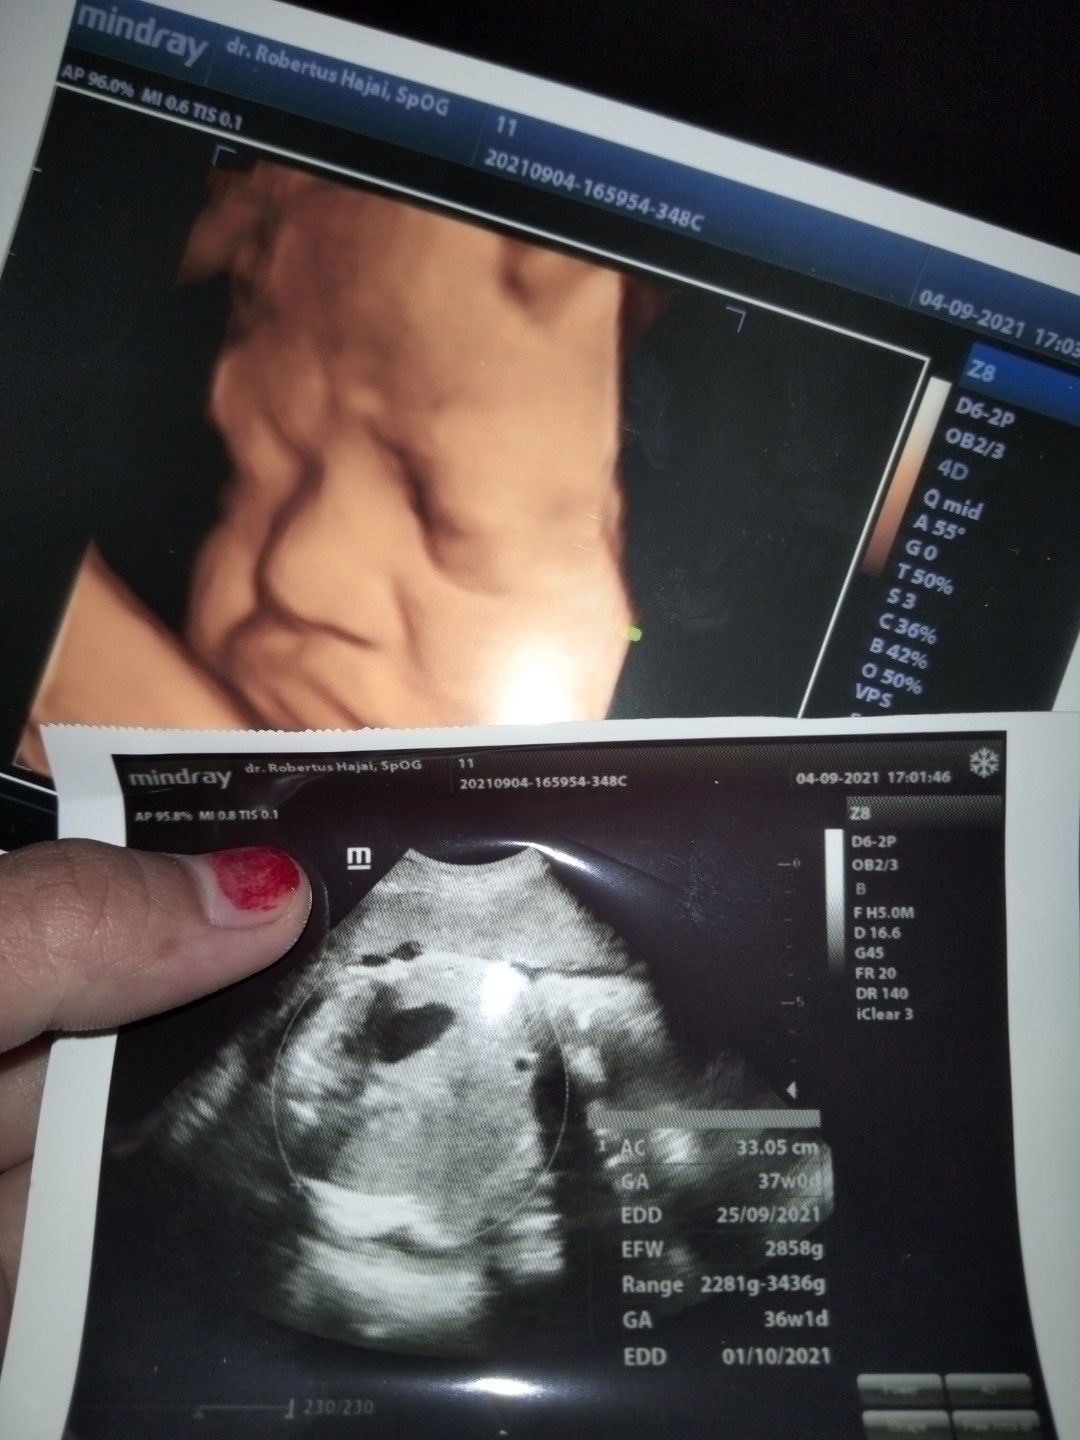

Wah jadi ikutan gasabar juga nih tapi apalah daya aku yang masih jalan 37week,semoga juga bisa segera dapet sinyal dari si utunku yg emes

UK nya sama bun kita 😇🙏 semoga kita segera dpt gelombang cinta dr dede dan lancar persalinannya ya bun amin 😇🙏